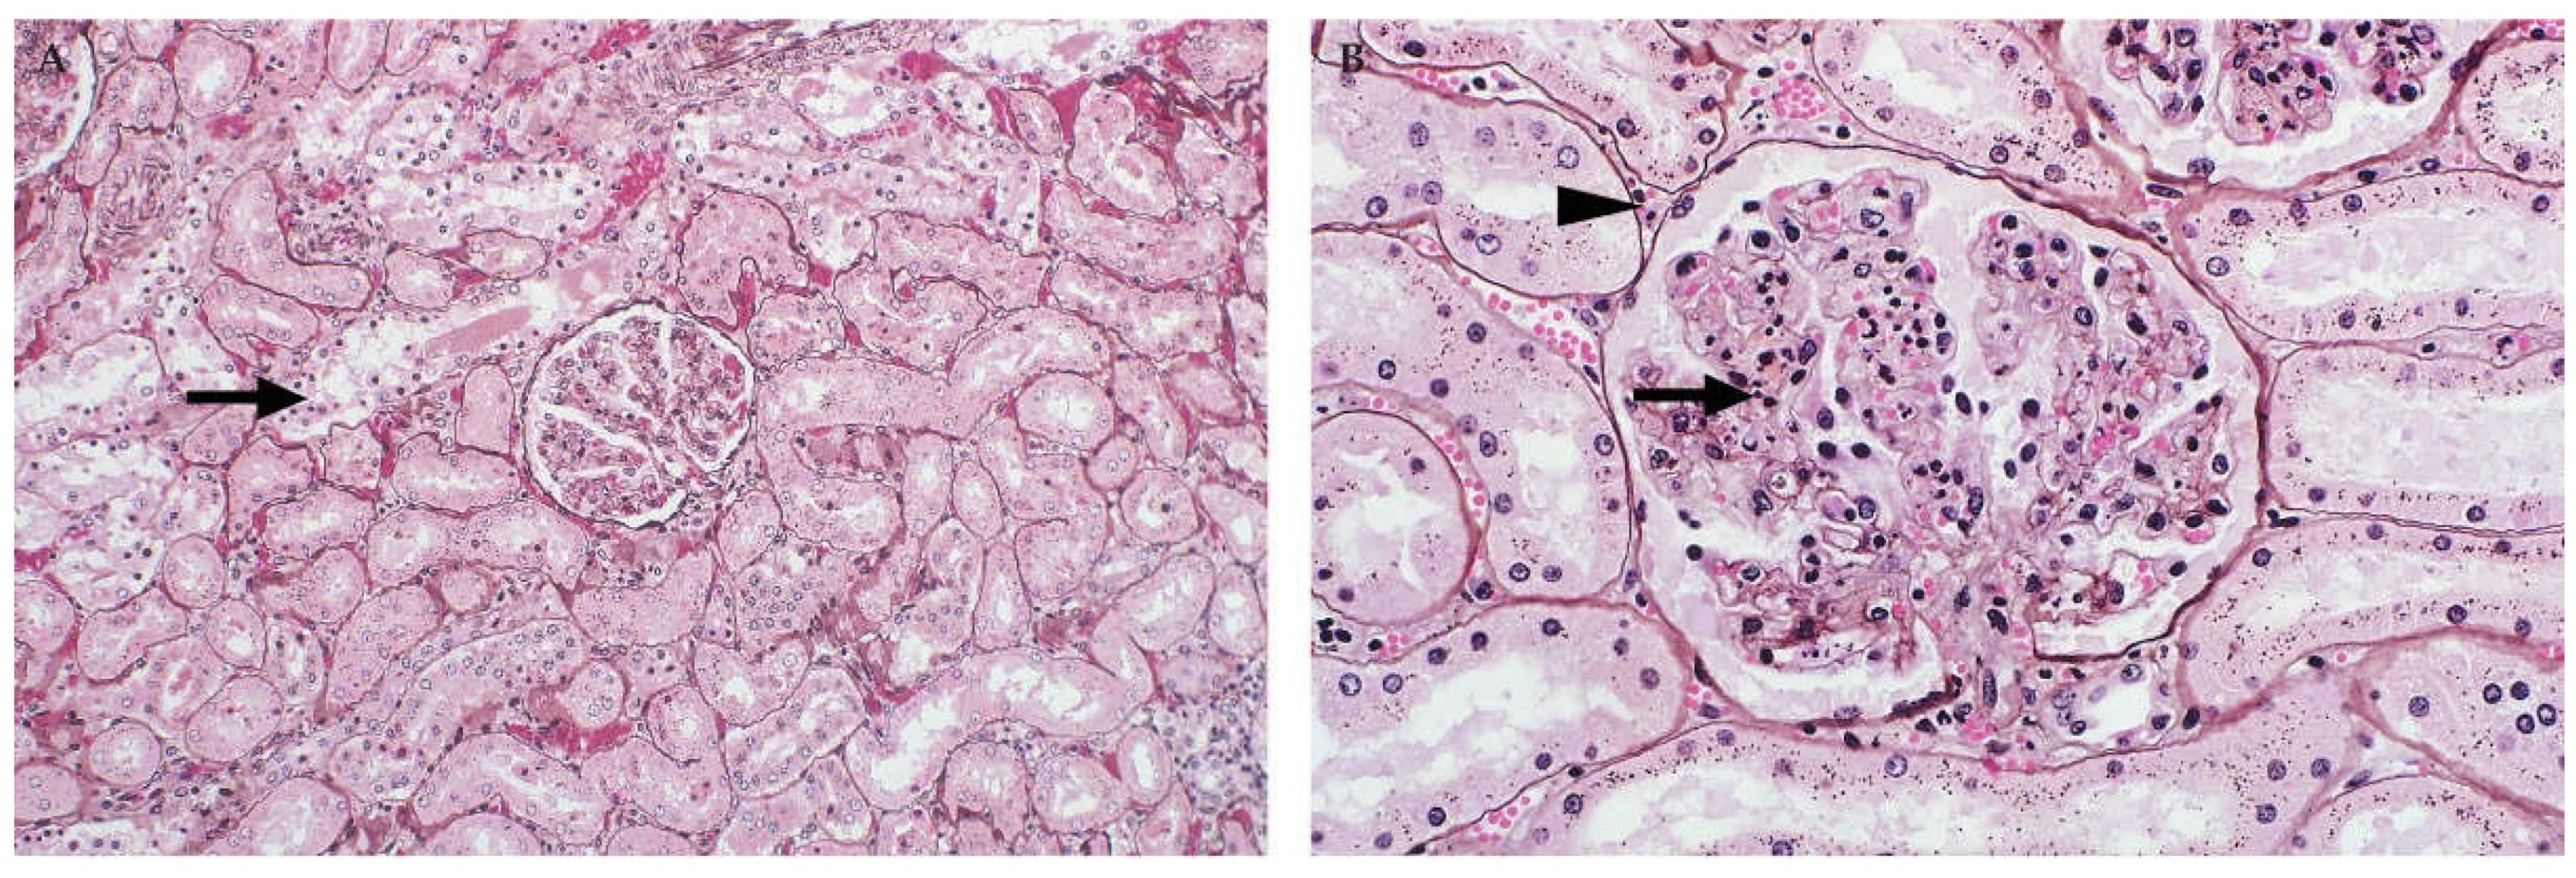

Figure 2.

Histopathology of the liver of cattle naturally infected with RVFV (Haematoxylin and eosin (H&E) stain). (A) Random multifocal to coalescing necrosis and haemorrhage (arrows), original magnification (mag) 40×. (B) Necrosis of hepatocytes extends into the periportal zones, specifically affecting hepatocytes of the limiting plate. Mild mononuclear cell inflammation (arrow) is also present in the portal area, mag 200×.

In calves and lambs less than a month-old, pale pinpoint subcapsular petechiae and foci of necrosis may be present in the liver and virtually all hepatocytes undergo necrosis (Figure 1) [32,35,46]. In foetuses, the liver usually does not have any discernible macroscopic lesions [37]. However, microscopically there is random dropout of hepatocytes from the reticulin framework which ranges from minimal to nearly diffuse hepatocyte necrosis. Haemorrhage or pooling of blood in spaces depleted of hepatocytes is inconspicuous in foetuses whereas oedema is present in the portal areas in most cases (Figure 2) [37]. Bile stasis is not present in any age category and bile ducts are not involved [32,35,37,45,46].